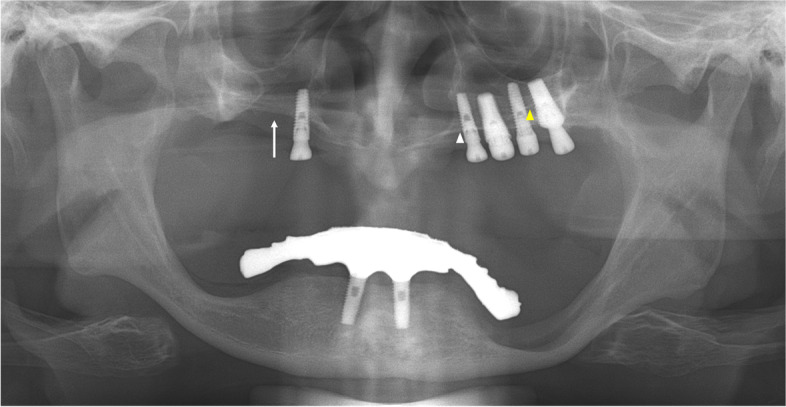

A 51-year-old woman was referred to our hospital on account of migration of the implant fixture to the superior cavity. The panoramic radiograph revealed that one implant fixture, which was intended to be placed in the premolar region, had been displaced superiorly (Fig. 1).

Panoramic radiograph of case 1 patient. The white arrowhead indicates the left hard palate line and the yellow arrowhead indicates the antral floor. The implant fixture is displaced into the superior cavity; however, the bone between the white arrows appears to have sufficient volume

The implant was observed horizontally between the boundaries of the nasal cavity and maxillary sinus, and it appeared that the fixture perforated the medial wall of the maxillary sinus. The fixture image was slightly enlarged and blurred. On computed tomography (CT) images acquired at the same time, the implant fixture was confirmed not in the maxillary sinus but in the nasal cavity (Fig. 2). It was completely different from what was predicted by the panoramic images.

In addition, on panoramic radiography, it appeared that a significant amount of bone was available between the lateral side of the nasal cavity and the medial side of the maxillary sinus. The implant fixture of the right premolar area appeared to be well placed with sufficient bone between the nasal cavity and maxillary sinus (Fig. 1), although the height of the alveolar bone was low. However, the acquired CT showed that there was insufficient bone in the area, and the implant in this area penetrated the nasal floor (Fig. 2d).